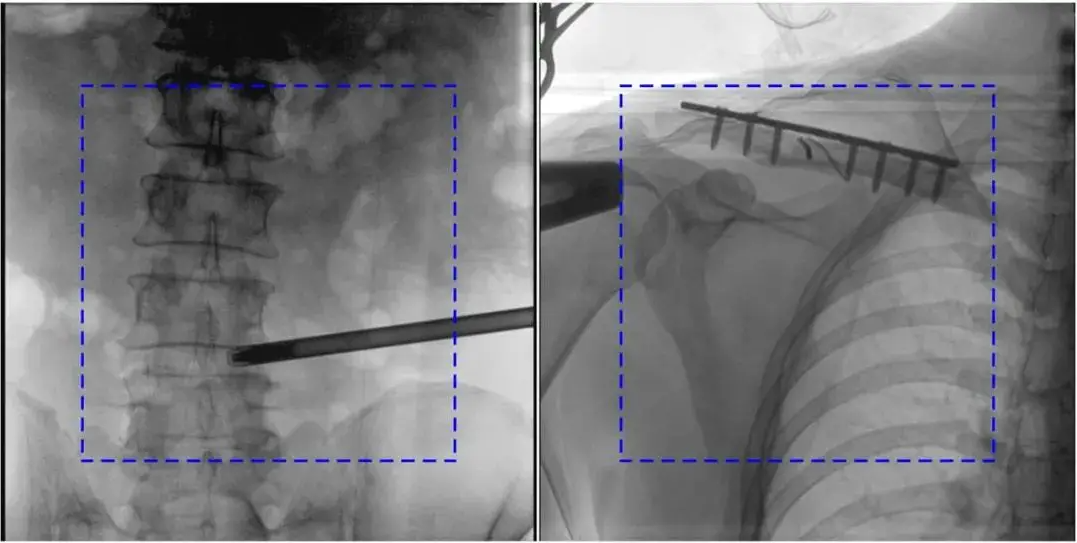

2. 自動曝光控制(AEC)異常

AEC模式下,金屬植入物或患者體位偏離視野中心可能導致曝光不足或過度。

解決辦法:手動調整曝光參數,確保感興趣區域位于視野中央;避免金屬干擾,必要時調整患者體位。